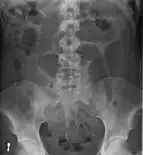

- Abdominal x-ray – tire-like shadow arising from right iliac fossa and passing to left

An x-ray of a person with a small bowel volvulus.

Plain X ray of a cecal volvulus